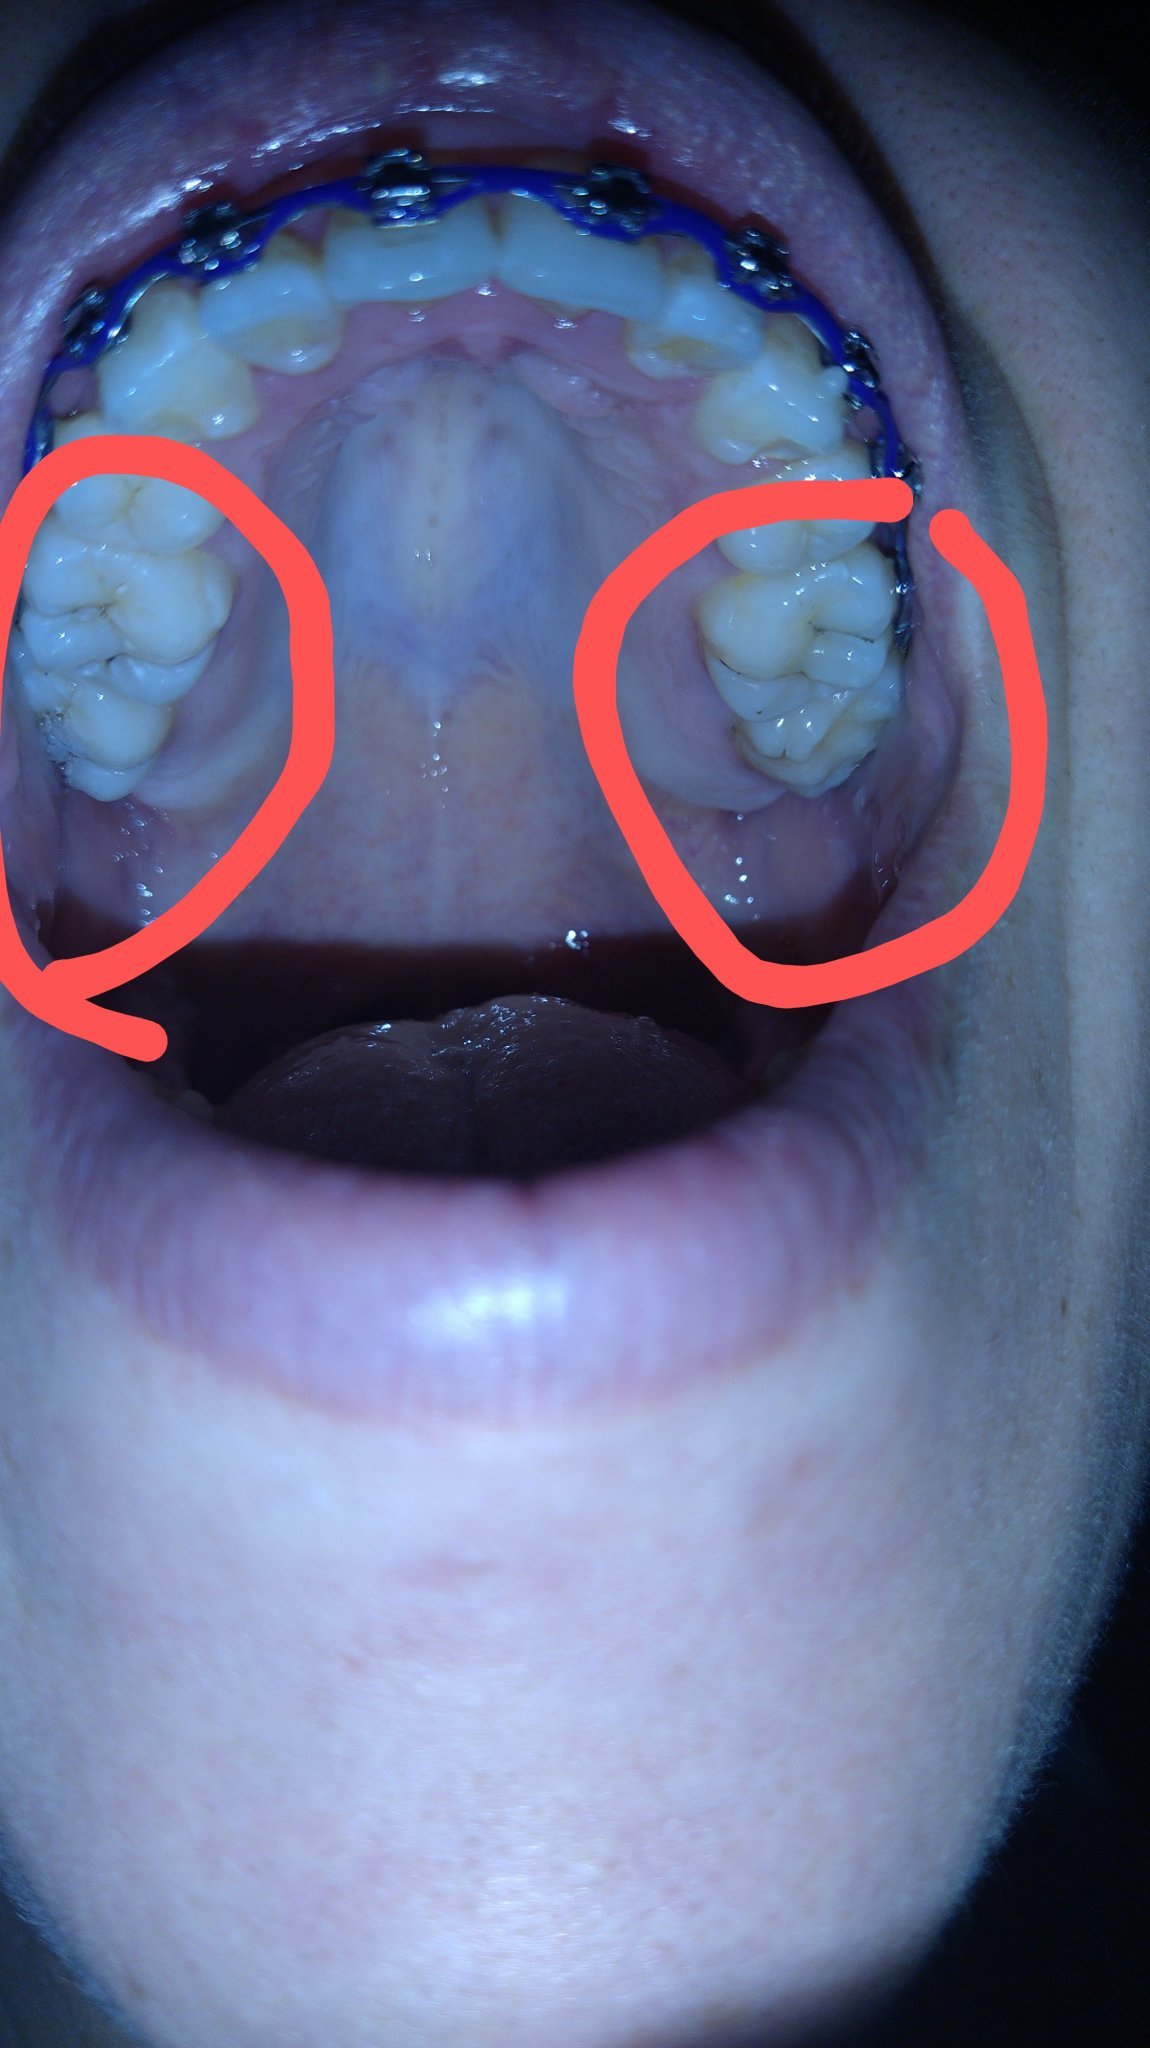

Здравейте и Честита Коледа ❤️Имам проблем ,последните ми зъби на горна челюст ми се изкривиха към бузите.На някой от вас случвало ли му се е,и как са се "обърнали" в правилна позиция?

Впредвид ,че съм с извадени четвърти зъби и извадени мъдреци и аз не знам кой номер са🤷И мъдреците ми бяха по същия начин изкривени.Часа за ортодонта ми е чак за януари,не ме е видял

Най-добре попитай ортодонта, ние само можем да гадаем. може да е само временно. Моите брекети ги носих преди 10 години, и се получи същото нещо. Сега като правих консултации за инвизалайн, го отбелязаха като част от проблема със захапката ми. Моите шести са смъкнати надолу и са единствените, които правят контакт, а седмите са ми щръкнали навън. Казаха, че ортодонтът е редил по шестите, вместо по седмите зъби. Затова ми предлагат да ми разширят захапката, като преместят кътниците настрани, но с правилен наклон надолу, да стане по-отворена U крива, вместо тясна.

Сега говорих с моята ортодонтка и тя каза,че така ще си останат.Аз имам контакт с долните,а странното е,че долните са си ми в правилна позиция.Объркана съм,страх ме е да не стане проблем за вбъдеще,и след няколко години отново да търся ортодонти😔

Да, седмите излиза да са значи. Не знам честно казано дали е ок така... Не мога да дам съвет за съжаление. Worried